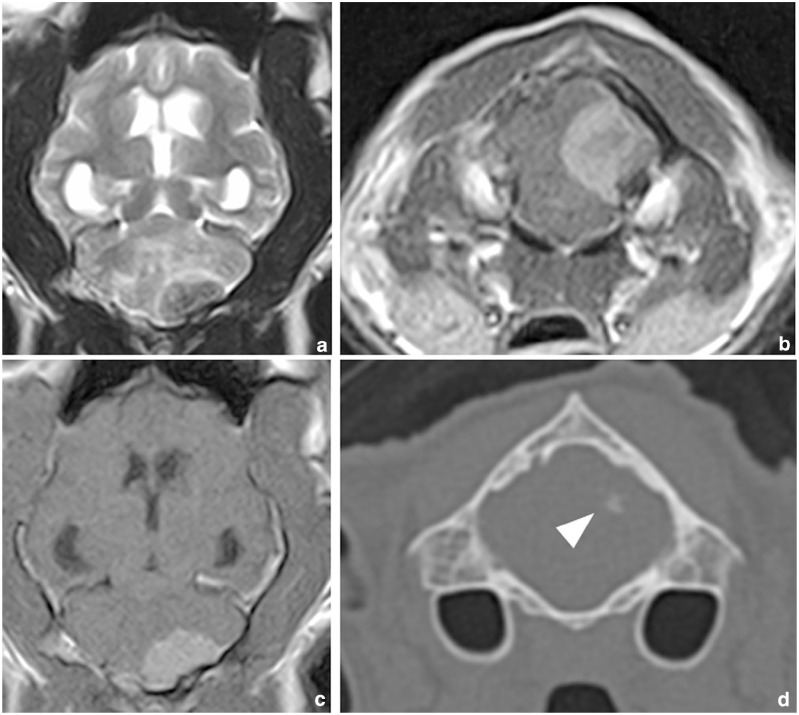

Case summary: A 13-year-old castrated male American Shorthair cat was referred for evaluation following a 3-week history of poor balance and decreased activity. The MRI findings revealed a well-defined left caudal cerebellar mass with a diameter of 1.2 cm, consistent with a meningioma. CT and MRI scans did not reveal metastasis. After a suboccipital craniotomy, the mass was resected subtotally as a result of parenchymal invasion. A histopathological examination revealed a benign fibrous meningioma with invasion into the cerebellum at the tumour margins. Postoperatively, the cat remained asymptomatic for 25 months, but ataxia recurred, and tumour recurrence was confirmed using MRI and post-mortem examination.

Relevance and novel information: This case demonstrates that even feline meningiomas with benign features can exhibit brain invasion. Since brain invasion is an indicator of malignancy in meningioma, a detailed histopathological evaluation of the tumour margins is essential for accurate grading and prognosis.